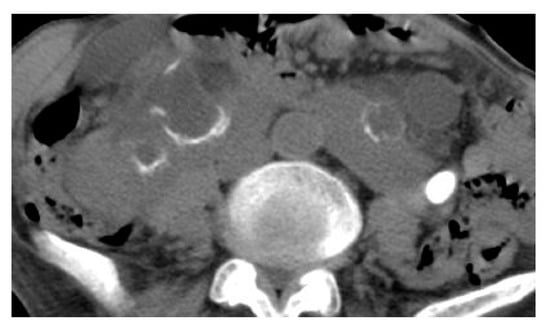

2.5. Xanthogranulomatous Pyelonephritis (XGP)

| Xanthogranulomatous Pyelonephritis | Non-functioning enlarged kidney, obstructing stone within a non-dilated renal pelvis, expansion of the calyces, and inflammatory changes in the perinephric fat. |